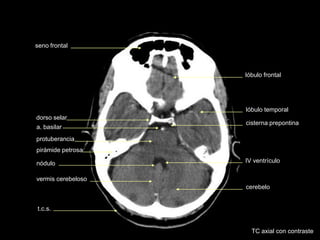

TC axial con contraste

lóbulo temporal

t.c.s.

seno esfenoidal

dorso selar

cerebelo

protuberancia cisterna del ángulo

pontocerebeloso

vermis cerebeloso

IV ventrículo

cisterna prepontina

a. basilar

lóbulo frontal

seno frontal

nódulo

pirámide petrosa